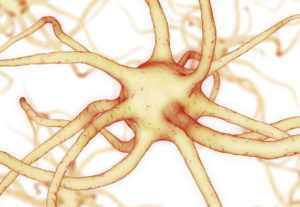

Attualmente ci sono circa 500 neurologi chiropratici che preferiscono, in linea con i principi della chiropratica, trovare soluzioni senza l’ausilio farmacologico. Essi tengono conto dello squilibrio che si crea quando l’interconnessione neurologica tra gli emisferi ed i lobi del cervello si sviluppa in modo inadeguato.

Questo squilibrio porterà inevitabilmente ad una maggiore possibilità di deficit motorio o cognitivo ed a disturbi comportamentali (vedi articolo Iperattivita’ e dislessia).

Diventano importanti quindi, trattamenti specifici e mirati per l’emisfero interessato per riportare un certo equilibrio come: esercizi vestibolo oculari, stabilometria, stimolazione visive, terapia dell’arte e l’Interactive Metronome (vedi articolo Metronomo interattivo).